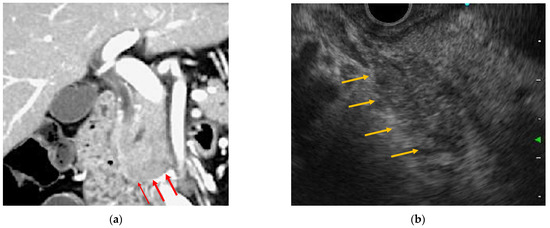

2.3.1. EUS

3.3.1. EUS